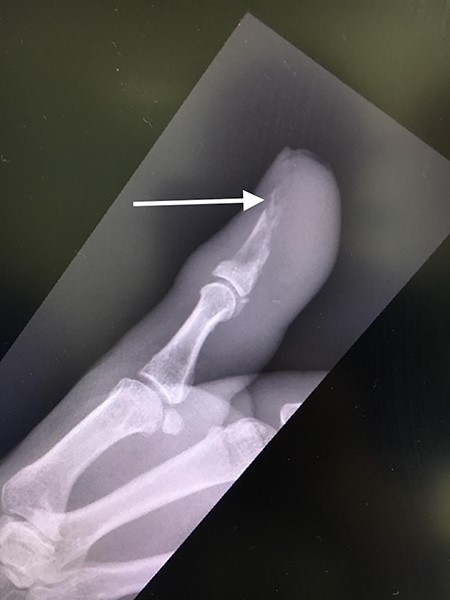

Her blood tests on presentation were unremarkable and X-rays of her right thumb showed a lytic lesion involving the tuft of the distal phalanx (Figs. 4 and 5). She was admitted to the hospital and was treated as having an infection of her right thumb with elevation and intravenous antibiotics. She underwent emergency surgery the next day for a washout and debridement of the right thumb. During the debridement in theatre, there was no pus in the pulp, but the bone was found to be eroded and soft, thus multiple specimens from the bone were sent for microscopy, culture and sensitivity, acid-fast bacilli (AFB) and histopathology.

AP radiograph of right thumb showing erosion of tip of distal phalanx.